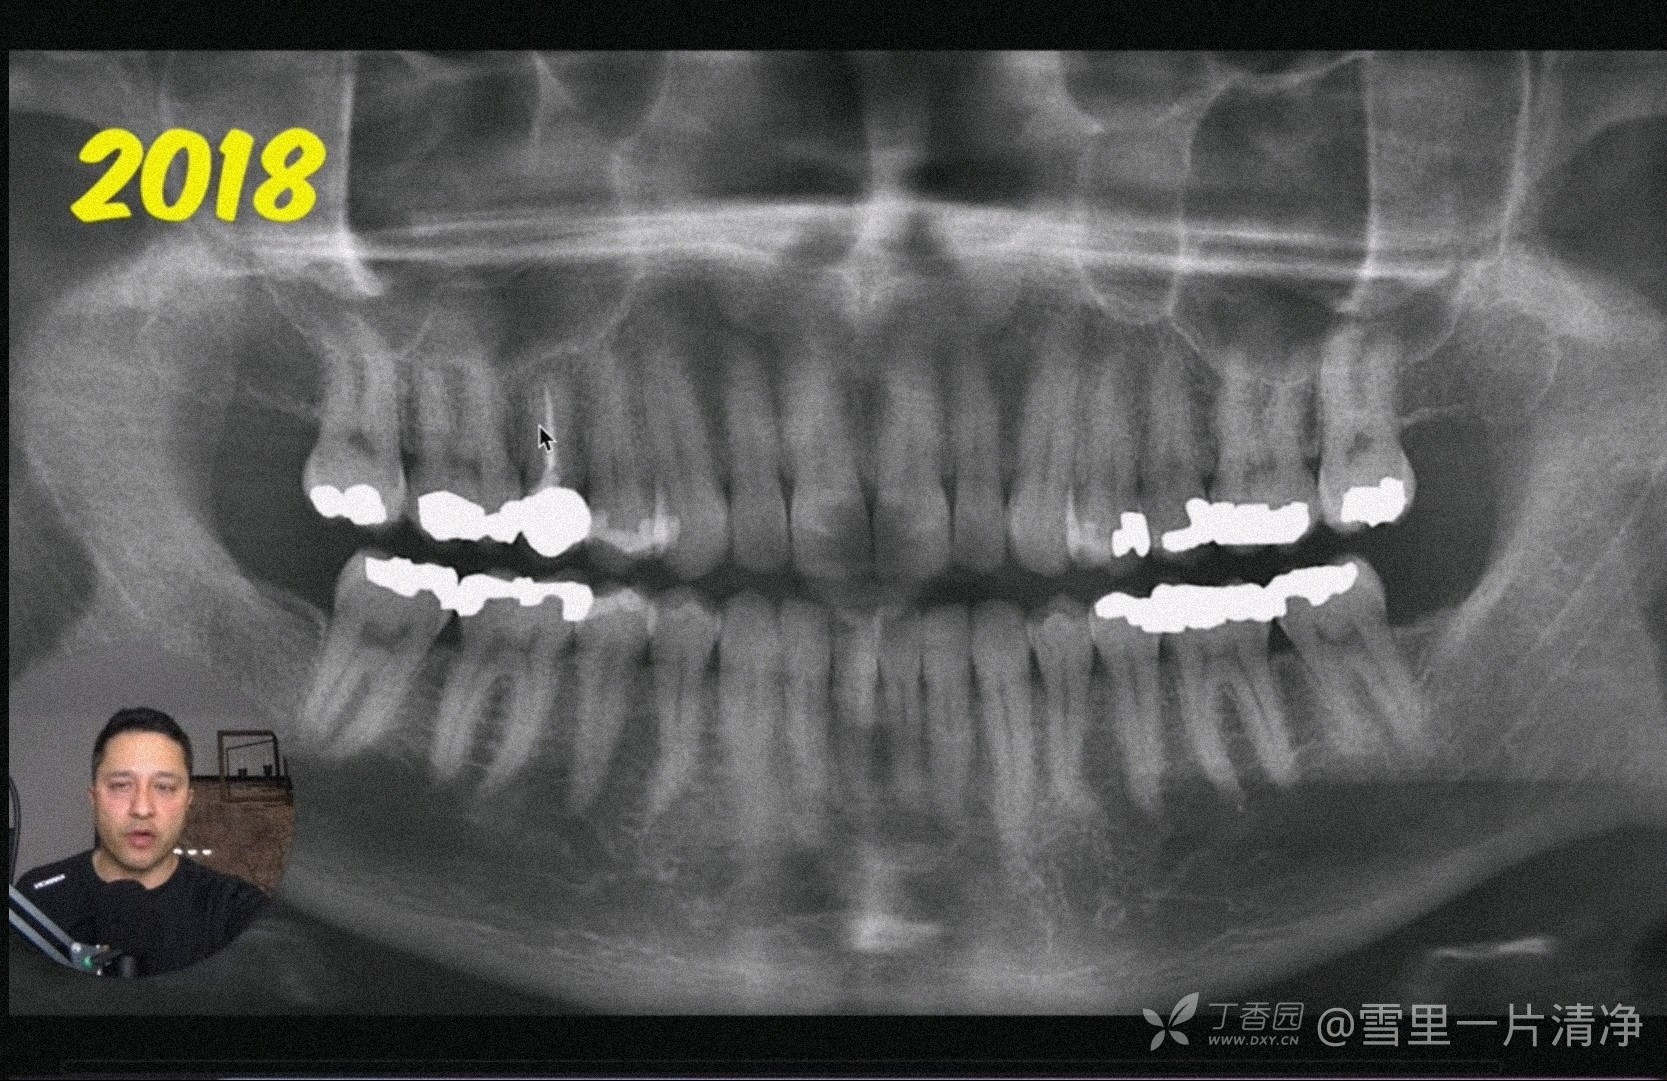

18年片子也OK